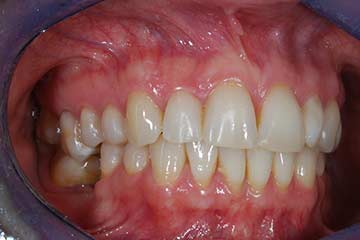

Con protesi fissa superiore e protesi fissa inferiore

I denti irrecuperabili dell'arcata superiore ed inferiore del paziente di anni 65

sono stati sostituiti da 10 impianti, cioè protesi radicolari endo-ossee che sostengono le protesi fisse superiore ed inferiore.